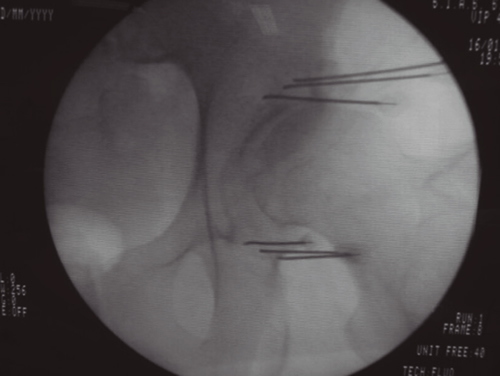

Figura 3